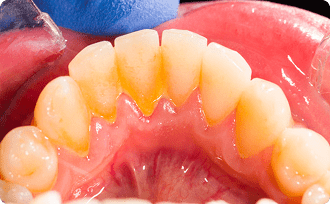

歯石

歯石はプラーク(バイオフィルム)が石灰化したもので、頑固にこびりつくため、ブラッシングだけで落とすことはできず、歯科医院で使用する専用の器具を使用して取り除くしかありません。また歯石は歯茎の上だけでなく、歯と歯茎の隙間して歯根の部分で歯石を作るため、歯茎の上の歯石を取り除いても歯根に付着している歯石を取り除かないと歯周病は改善しません。歯周病が改善しない人の多くは歯根に歯石が付着してることが多いです。